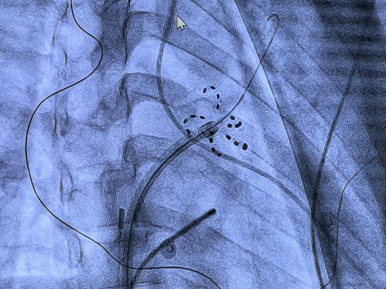

9月19日,在心脏内科姜建教授、付华教授的带领下,我院心脏内科电生理亚专业组曾锐教授团队在麻醉、护理团队的通力配合下,应用FARAPULSE脉冲导管消融+Watchman FLX左心耳封堵,为一例阵发性房颤患者完成一站式手术。手术使用的FARAPULSE一次性心脏脉冲消融导管,今年7月获批国内上市,我院作为首批开展的医疗机构,为房颤患者提供了药物、射频消融等传统治疗方式以外新的器械治疗方案,有望达到一次治疗、长期稳定心脏节律以及预防卒中的效果。

相比射频消融,脉冲消融具有组织选择性,不易损伤毗邻组织,同时通过非热能的消融方式,安全性得到提升,每次放电仅需2.5秒,缩短整个手术时间。手术使用的一次性心脏脉冲消融导管,是全球首个上市的脉冲消融技术器械,其安全性和有效性拥有全球最多的临床研究数据支持。手术中消融过程左心房操作时间仅18分钟,相较其他消融方式,极大提升了手术效率,更好地让患者获益。

左心耳封堵器通过封堵左心耳来预防房颤时在左心耳内血栓的形成,从而降低房颤患者由血栓栓塞引发长期残疾或死亡的风险。同时,经皮左心耳封堵通过微创治疗方案可消除患者对长期口服抗凝治疗的依赖性,为患者提供治疗新选择。